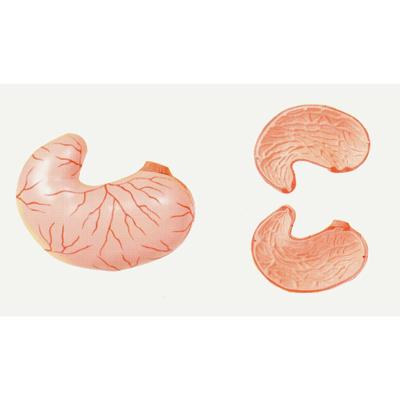

Stomach